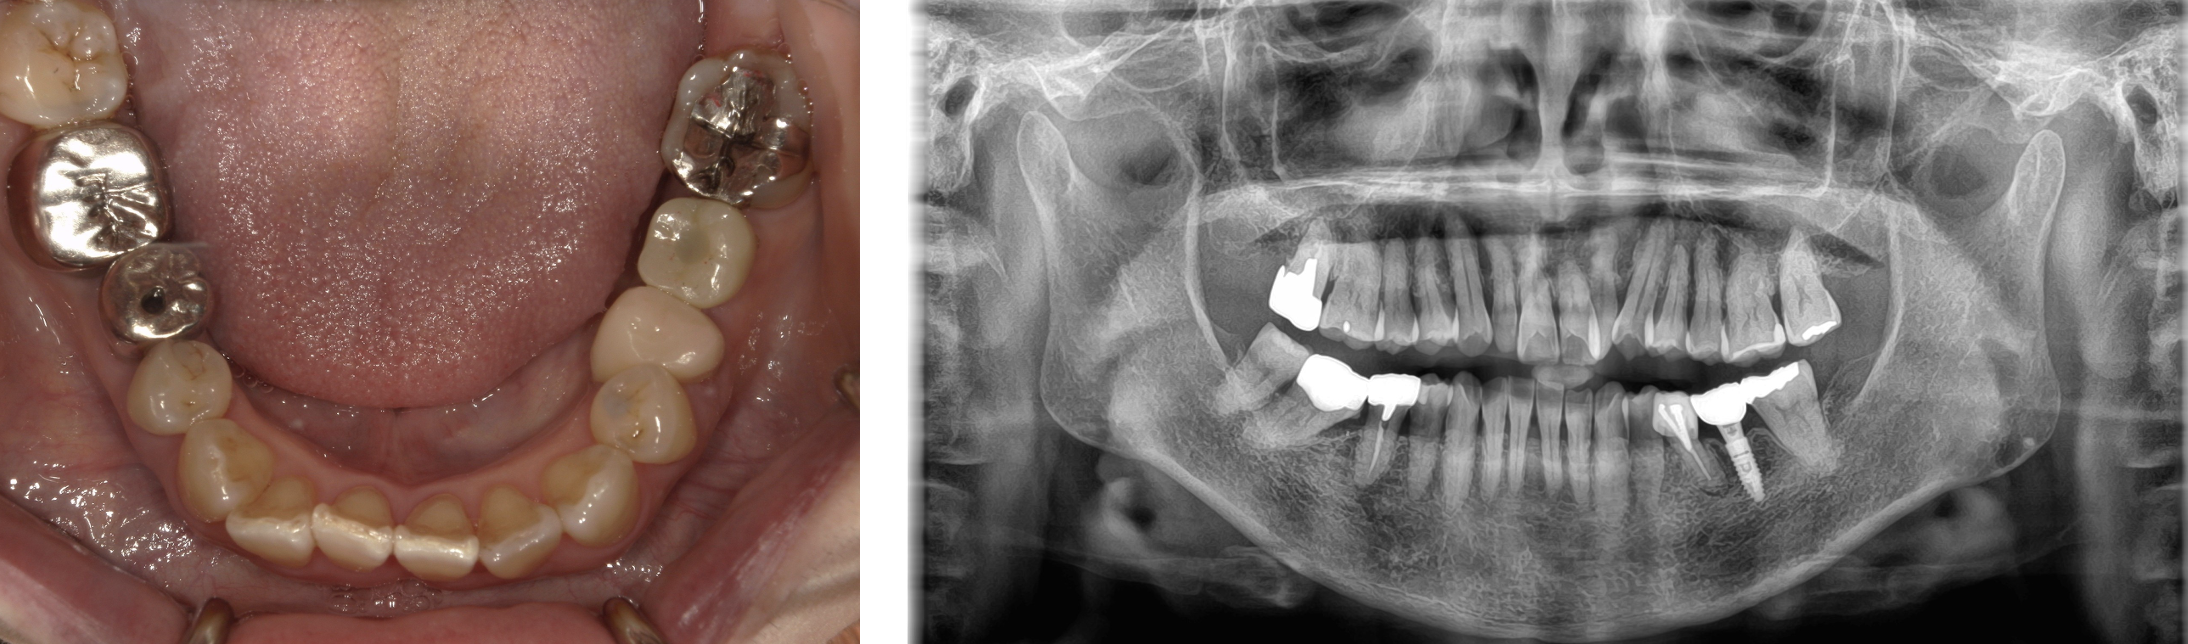

インプラント 症例1

左下6番にインプラントを行った症例

ブリッジからインプラントに変更